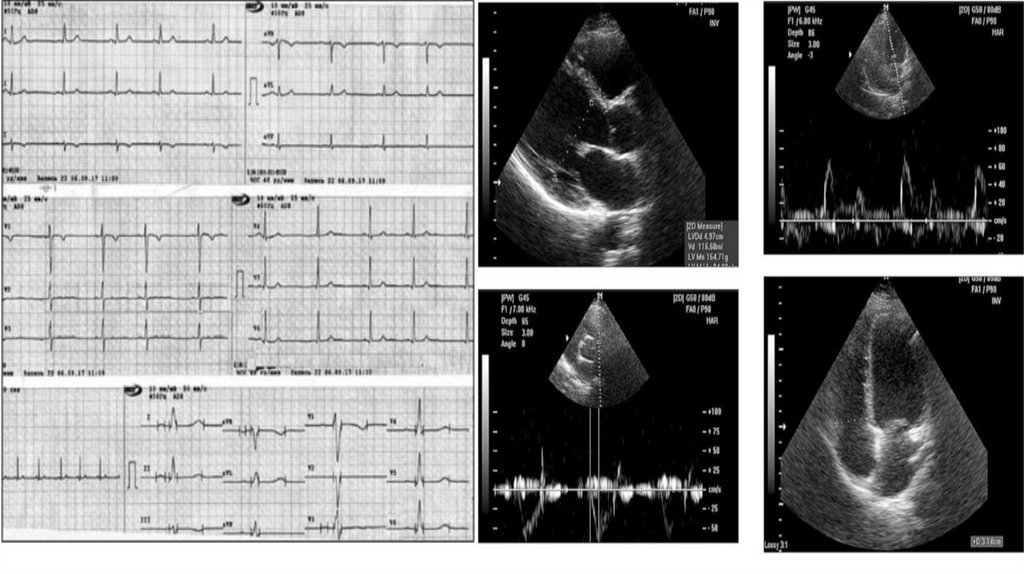

6. Діагностика

ДІАГНОСТИКА